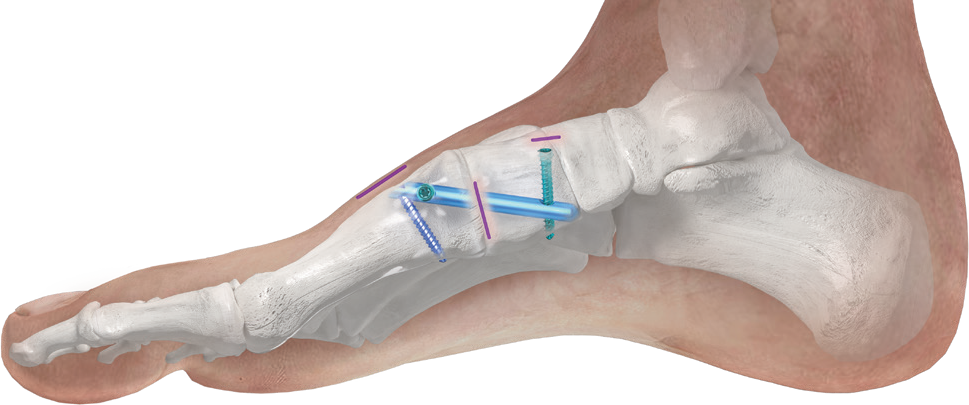

The Phantom® MIS System was created to support a minimal approach to joint preparation for a Lapidus Arthrodesis procedure. This first-of-its-kind system allows the ability to access the 1st Tarsometatarsal (TMT) joint with minimal disruption to the soft tissue and overlying skin.

The Phantom® Nail is completely inserted into the bone, which minimizes concerns of irritation with shoe wear post-surgery⁷.

PHANTOM® MIS NAIL

The Phantom® MIS procedure is designed to correct your bunion with three separate incisions, which are each 0.4 inches or less. This procedure requires shorter incisions than traditional approaches leaving you with far less scarring.

The Phantom® MIS (Minimally Invasive Surgery) procedure is a first of its kind approach which offers revolutionary fixation within the bone, designed to minimize discomfort associated with traditional bunion procedures. This technology and approach stabilizes the correction through three very short incisions, leaving you with a cosmetically appealing result when compared to traditional approaches.